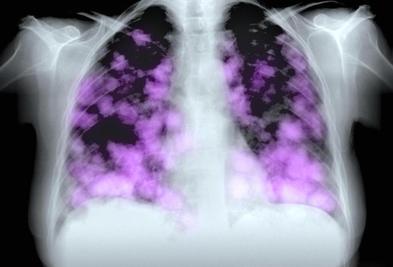

为什么肺癌会夺走人们的生命?看完这篇文章,你会重新认识肺癌。 原创 胡洋大夫 呼吸科胡洋医生 首先,肺癌不是一种局部疾病,而是一种器质性疾病。虽然它生长在肺部,但它可以通过各种方式影响全身,如内分泌系统,这会导致人们缺乏力量、食欲不振和某些疾病。 肺癌可以产生无 2025-05-21

肺癌只要长出来,肯定会出现几种现象,有时早期发现对生命没有威胁。 原创 胡洋大夫 呼吸科胡洋医生 1、只要你有肺癌,就会有肺结节或肿块。有没有没有没有肺肿块的肺癌?我确实见过,但极其罕见。这类患者的肺部没有疾病,但纵隔肺门淋巴结肿胀,最终被证明是肺癌。大多数癌症患者 2025-05-21